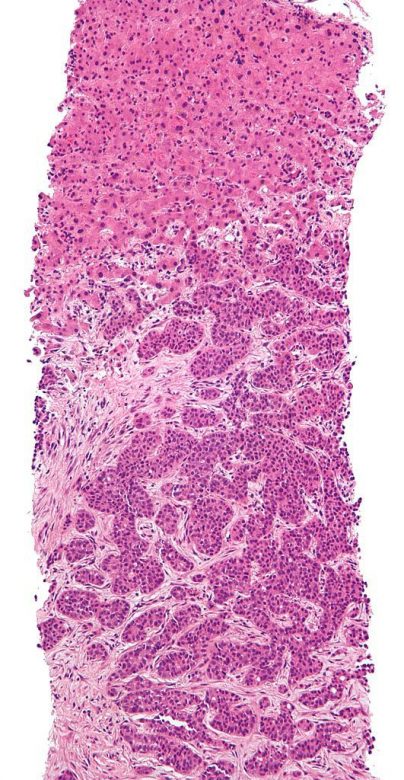

Image Credit: Nephron / Wikimedia Commons.

Anal cancer

“Anal cancer cases have been increasing over several decades. Infection with human papillomavirus (HPV) is the major risk factor for anal cancer.

“Signs of anal cancer include bleeding from the anus or rectum or a lump near the anus. Tests that examine the rectum and anus are used to detect (find) and diagnose anal cancer. Certain factors affect the prognosis (chance of recovery) and treatment options.”